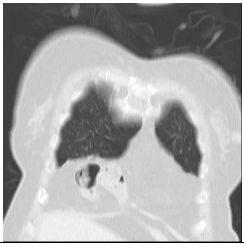

2. A 27-year-old woman had productive cough for one month.